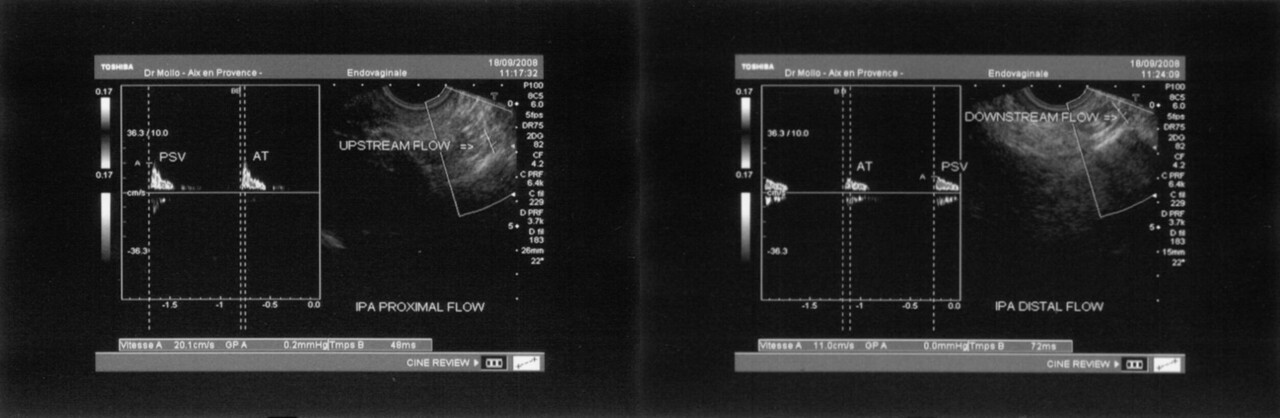

L’électromyogramme (EMG) n’est plus utilisé pour le diagnostic de compression du nerf pudendal.4,5 L’écho-Doppler des artères pudendales, en revanche, peut orienter vers le diagnostic de NP par compression canalaire, avec une bonne sensibilité (89  %), mais une spécificité de seulement 67  % (fig. 3).6

6. Mollo M, Bautrant E, Rossi-Seignert AK, et al. Evaluation of diagnostic accuracy of colour duplex scanning, compared to electroneuromyography, diagnostic score and surgical outcomes, in pudendal neuralgia by entrapment: A prospective study on 96 patients. Pain 2009;142:159-63.